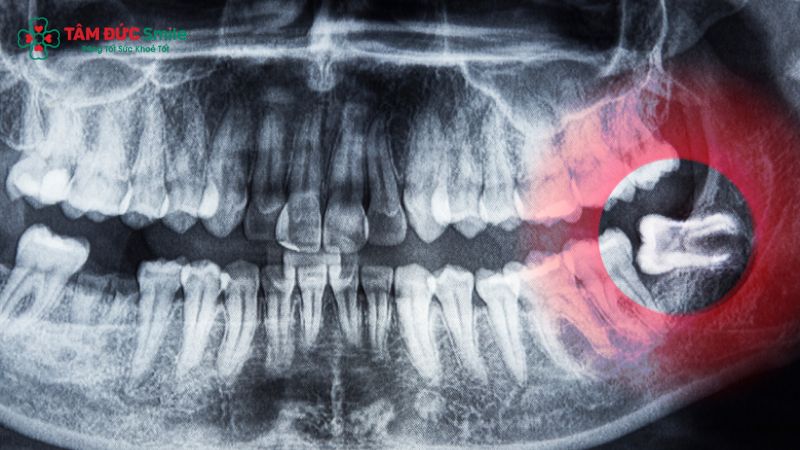

Răng số 8, hay còn gọi là răng khôn, thường mọc trong độ tuổi trưởng thành, từ 17 đến 25 tuổi – giai đoạn xương hàm đã phát triển ổn định. Tuy nhiên, do không còn đủ khoảng trống để mọc đúng vị trí, răng khôn rất dễ mọc lệch, mọc ngầm, gây chèn ép răng kế cận, gây đau, viêm lợi, thậm chí làm sai lệch khớp cắn.

Việc nhổ răng số 8 trong các trường hợp này là bắt buộc, nhằm loại bỏ nguy cơ viêm ổ răng khô, nhiễm trùng, hoặc tiêu xương hàm kéo dài. Ngoài ra, răng số 8 không có chức năng ăn nhai rõ rệt và thường tiềm ẩn nguy cơ ảnh hưởng đến răng kế bên, khiến việc điều trị tốn kém hơn nếu không can thiệp kịp thời.

Sử dụng máy CT Cone Beam 3D, bác sĩ sẽ chụp phim để xác định chính xác vị trí mọc của răng khôn, hướng mọc, mức độ ảnh hưởng đến răng kế cận và dây thần kinh dưới nướu.

Thông tin này là cơ sở để lên kế hoạch nhổ răng an toàn, tránh tổn thương các dây thần kinh quanh vùng hàm.